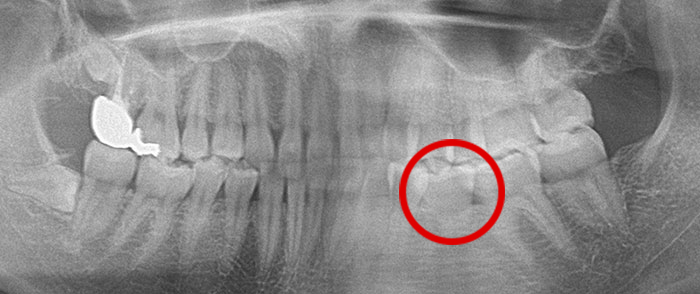

横になった親知らずの症例

Before

真横になった親知らずを抜歯したレントゲン写真です。